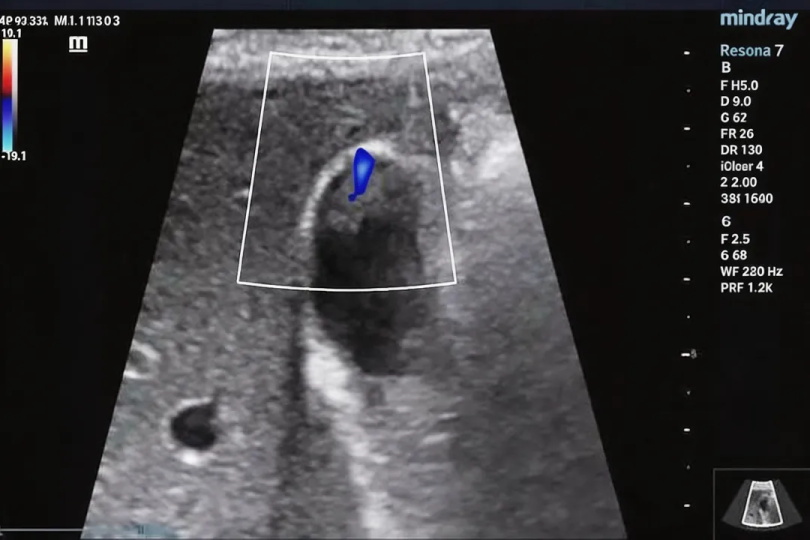

怎么发现胆囊息肉?首选超声就够了

很多人都是在中科体检做腹部超声时,偶然发现胆囊息肉的??这也正是超声的优势:无创、方便、价格实惠,还能重复检查,特别适合用来筛查和长期随访,也是中科体检成人必检套餐中不可或缺的核心项目之一。

640 (2).jpg

只有一种情况需要进一步检查:如果中科体检的超声提示息肉比较大、形态看起来可疑(比如不规则),或者医生怀疑有恶变可能,就会建议做上腹部增强CT或磁共振,进一步判断息肉的性质,这也是中科体检精准深度筛查套餐中的重要补充项目。